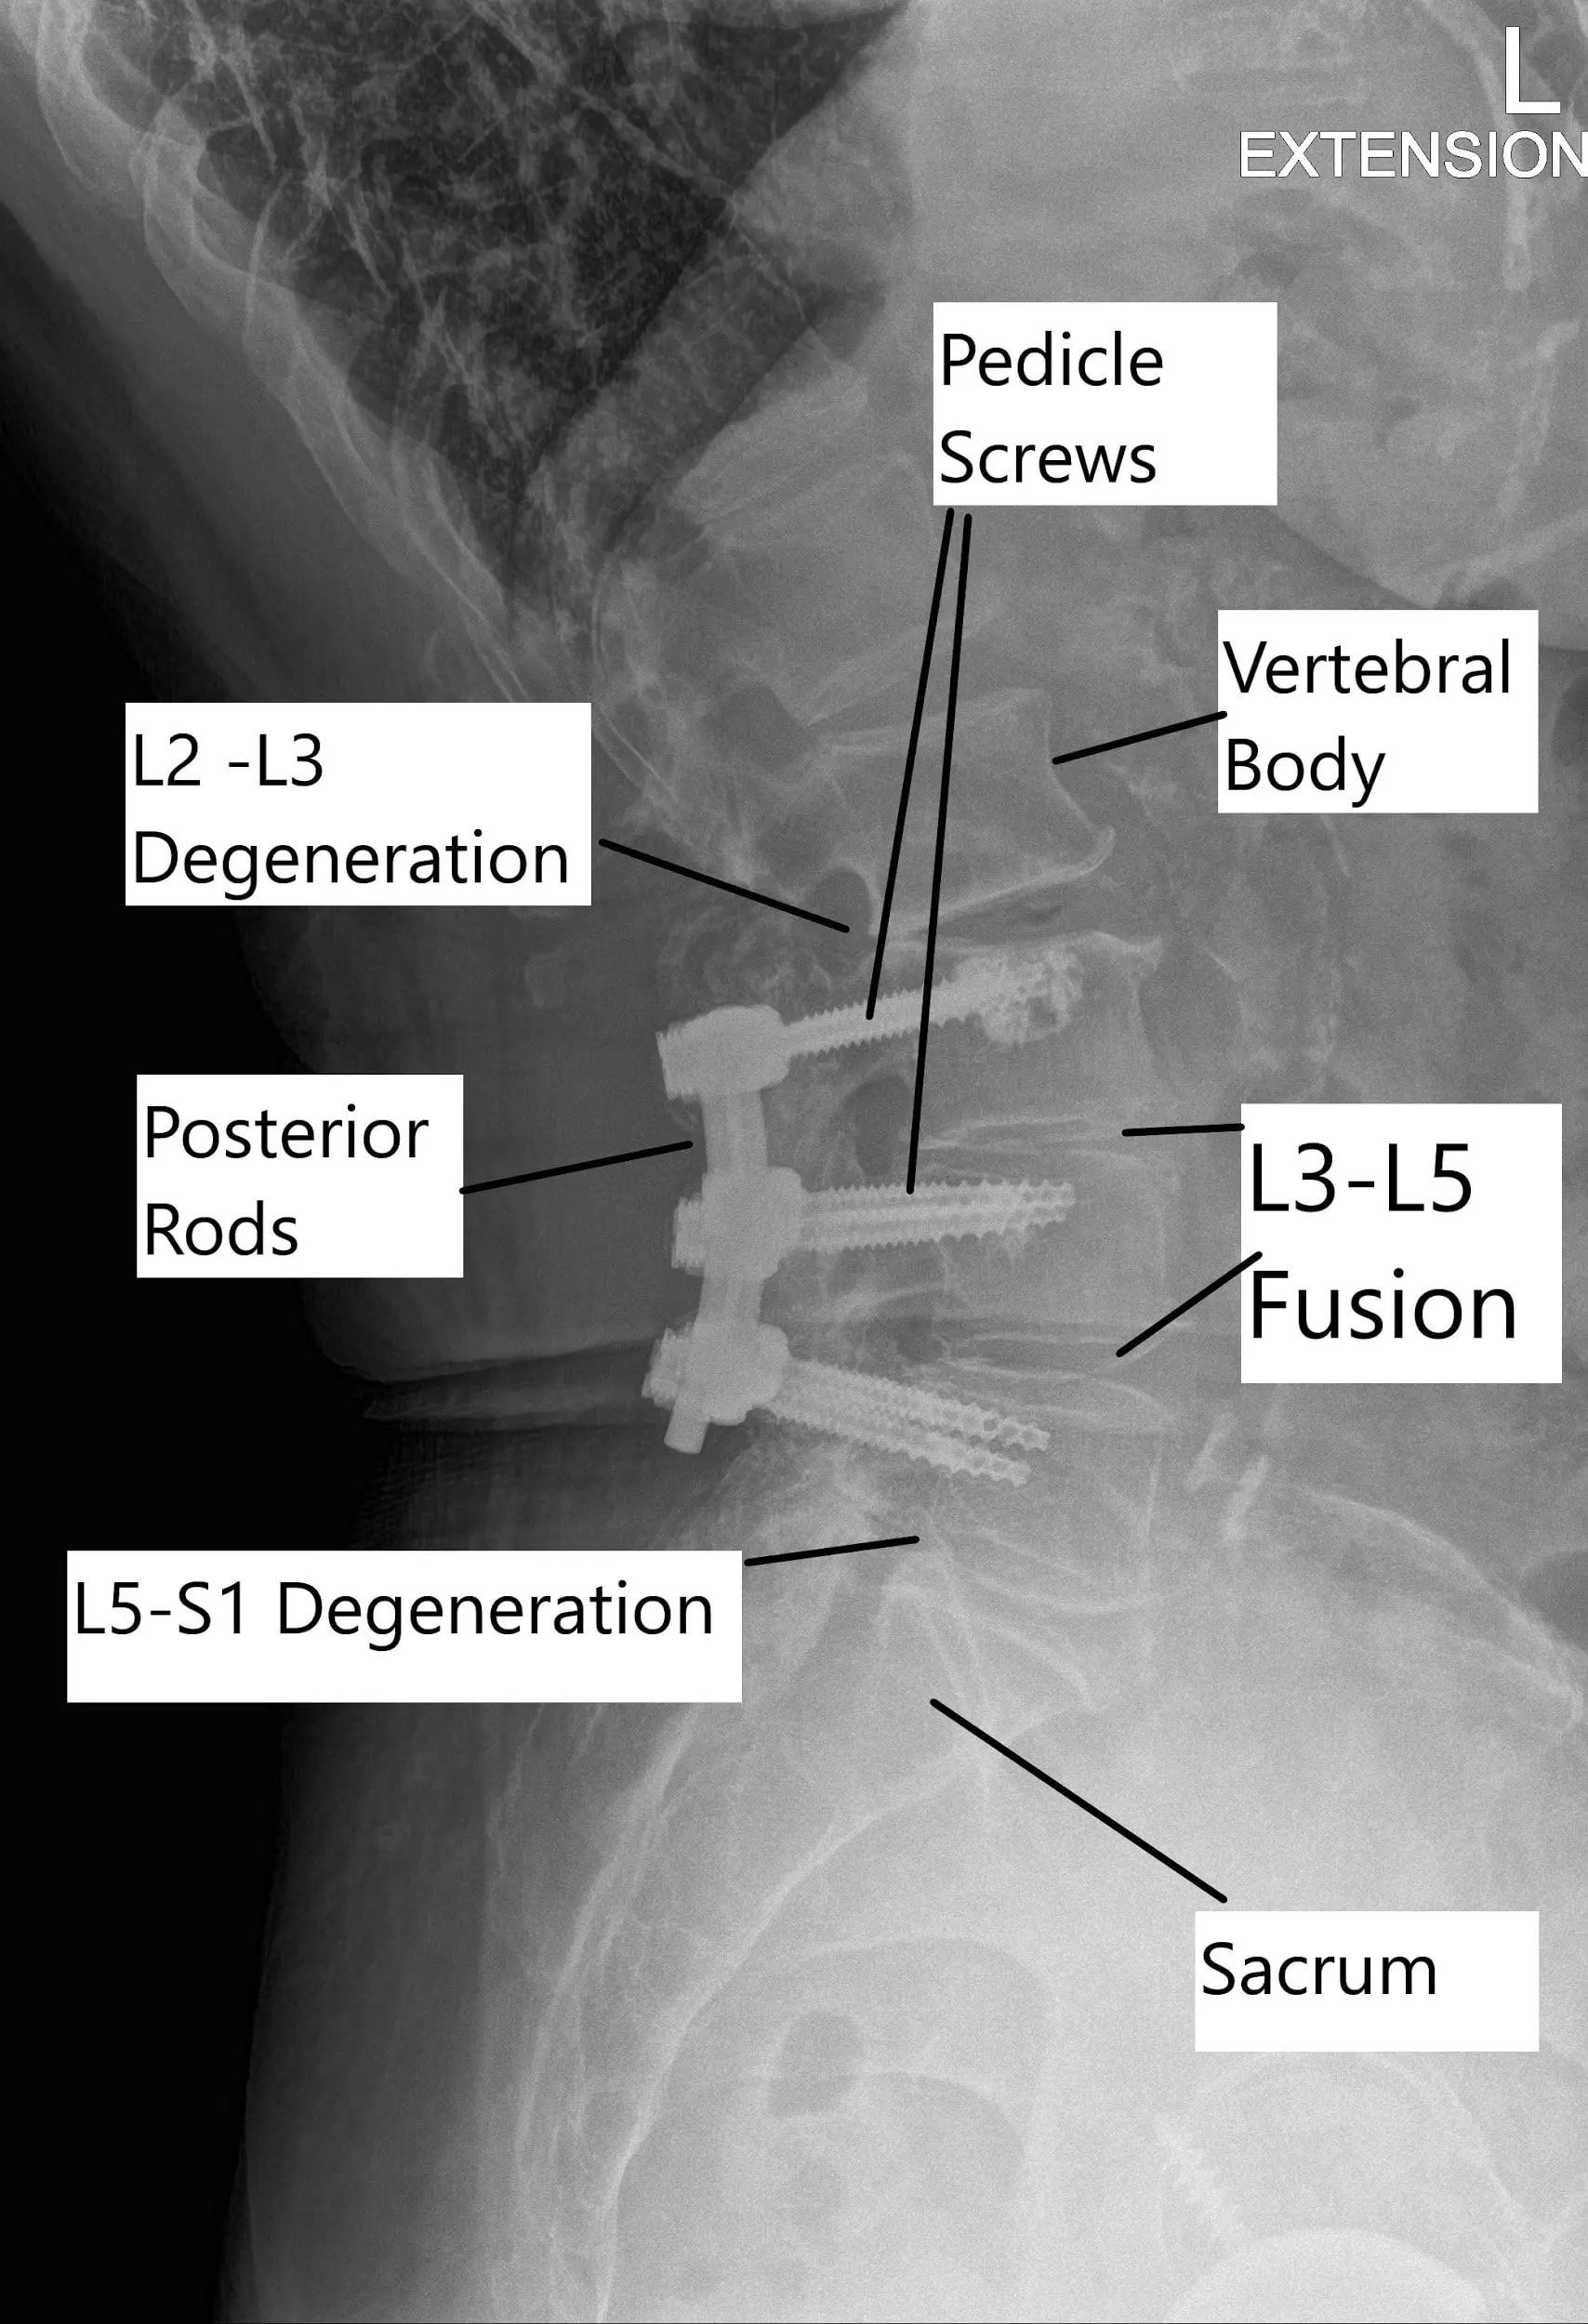

Status post L3 to L5 fusion with adjacent segment degeneration of L2-3 and L5-S1 on X-ray.

The spine is composed of vertebrae separated by intervertebral discs, which act as cushions. In spine surgery, the goal is often to alleviate pressure on nerves or stabilize the spine. A spinal fusion procedure involves joining two or more vertebrae together to prevent movement at the affected segment. When this fusion fails, the vertebrae may shift, causing additional pain or nerve compression. Adjacent segment degeneration occurs when the vertebrae adjacent to a fusion site begin to deteriorate due to increased stress from the lack of motion in the fused segments.

Transition syndrome results from the instability of the segments adjoining the fused segment in surgery. The additional stress on the adjoining segment due to the successful fusion of diseased level may result in accelerated degenerative changes in the adjoining level.

- Adjacent segment degeneration: Degeneration of vertebrae next to a previously fused segment.

The images above show various types of instruments used in posterior spinal fusion which may be used for revision surgery. The rods are used to stabilize the spinal segments and are tightened over the pedicle screws. The rods may be contoured to a required shape during the surgery to achieve maximum stability using the rod benders.